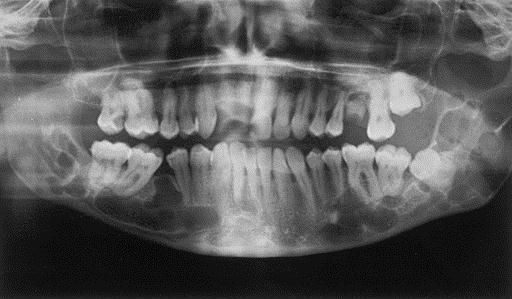

Что видно на рентгеновских снимках челюсти и молочных зубов у детей

Рентген зубов у детей (дентальный) проводится чаще, чем у взрослых. Популярность рентгенографии в стоматологии обусловлена